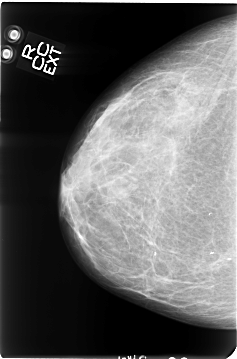

B_3047_1.RIGHT_MLO

RIGHT_CC LINES 4664 PIXELS_PER_LINE 3080 BITS_PER_PIXEL 12 RESOLUTION 50 NON_OVERLAY